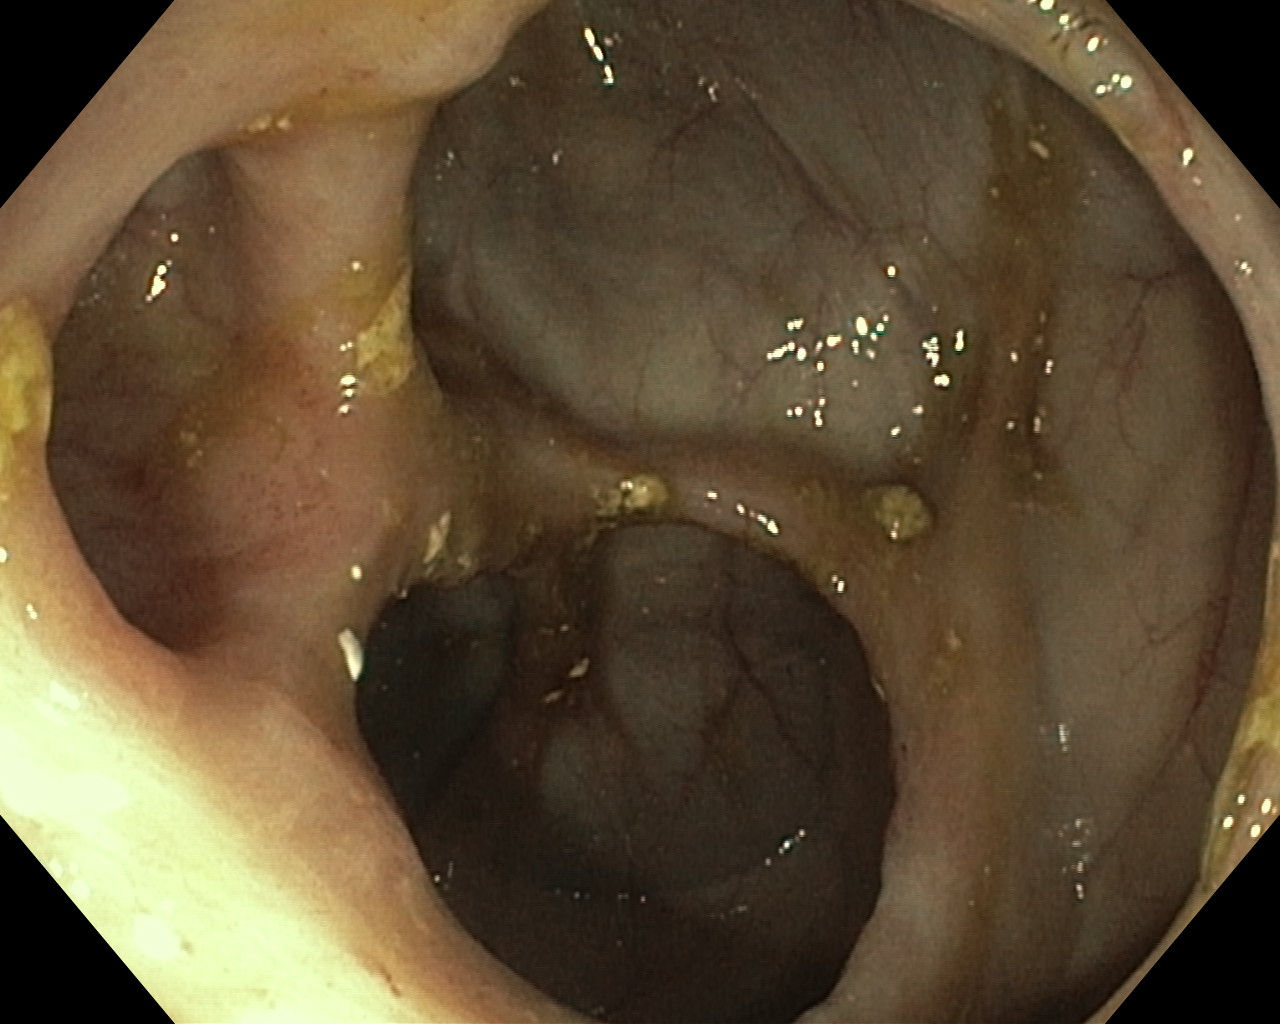

Obrazy endoskopowe

Choroba Leśniowskiego-Crohna